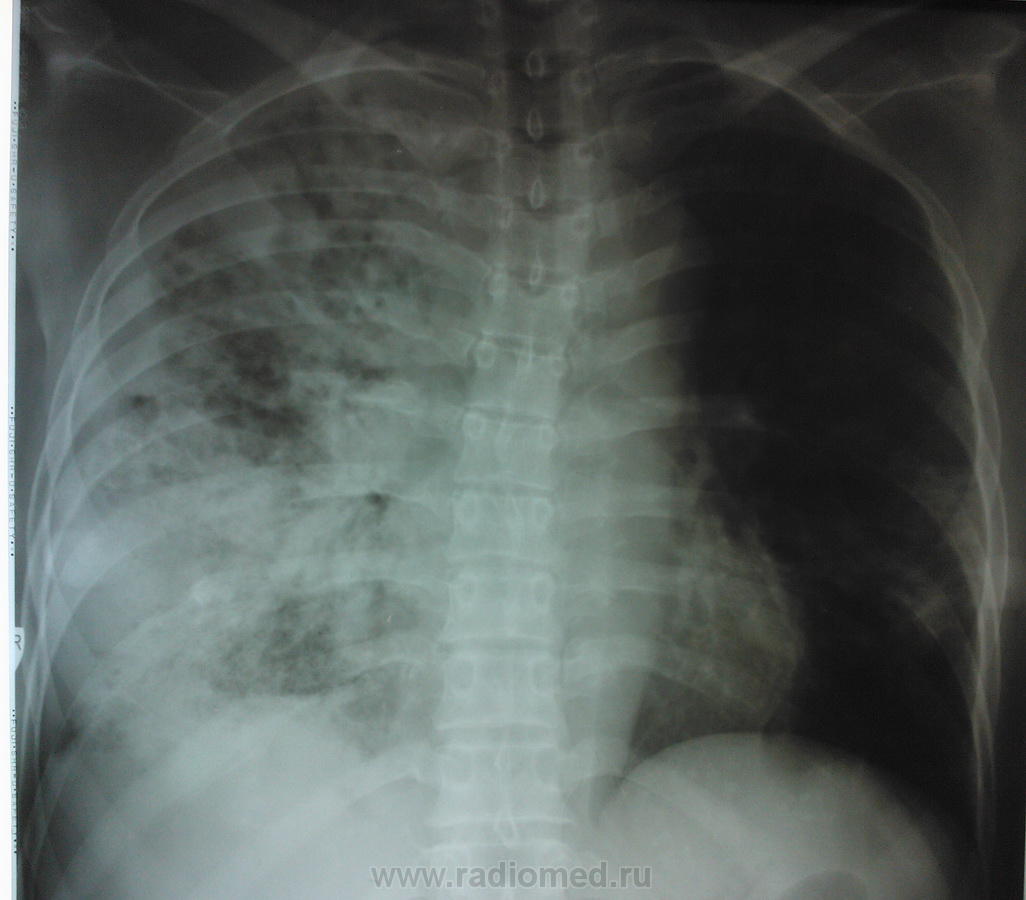

Женщина пенсионного возраста поступила в отделение сестринского ухода при терапии с диагнозом "Алкогольная интоксикация", жалоб особых нет, раннее не обследована, из анамнеза злоупотребление алкоголем. после проф. флюшки отправлена на консультацию к онкологу и фтизиатру. фтизиатр свое исключает и также отправляет к онкологу, онколог рекомендует КТ ОГК, на КТ врят ли поедет так как из глухой деревни, в анализах крови ничего особенного, хотеллось бы узнать мнения коллег по данному случаю.

Начинаем диф ряд от рака, формирующегося абсцесса и тбц.

Случай достаточно непростой. Сразу обратил внимание на выраженую компенсаторную эмфизему левого легкого. Правое значит очень плохо функционирует. И причиной этого может быть и обширность поражения, и бронхообструкция, и то и другое вместе. Полости могут быть и при туберкулёзе, и при абсцедирующей прневмонии, и при раке с распадом. Абсцесс вроде бы не вписывается в лабораторные показатели, но у хронических алкоголиков может быть убитый иммунитет. Туберкулез, на мой взгляд, при такой обширности, должен был дать отсев и в другое легкое. Так что, из этих рассуждений больше склоняюсь к раку. В таком неоднозначном случае всеравно следует оставить диф. ряд: рак, тбц, абсцедирующая пневмония и уговорить пациента на КТ, бронхоскопию.

По-моему это типичная картина активного туберкулеза - инфильтраты со склонностью к слиянию, очаги с нечеткими контурами.. Средостение смещено вправо, что может указывать на фиброз в правом легком.. Спокойные анализы, неяркая клиника туда же - к туберкулезу. На каком основании фтизиатр так быстро сказал, что это не его?

Формально по рентгенограммам, особенно прямой, в первую очередь, на мой взгляд, можно подумать о гангрене правого лёгкого. Правда такой диагноз у многих вызывает неприятие.

сегодня пациентке провели контрольную R-графию (снимок только в прямой проекции и на другом аппарате - немного "мягче", предыдущий сломался, а этот боковой не смог снять), сравнить тяжело (на разных аппаратах, разная экспозиция и тд и тп) но по мне динамика отрицательная.